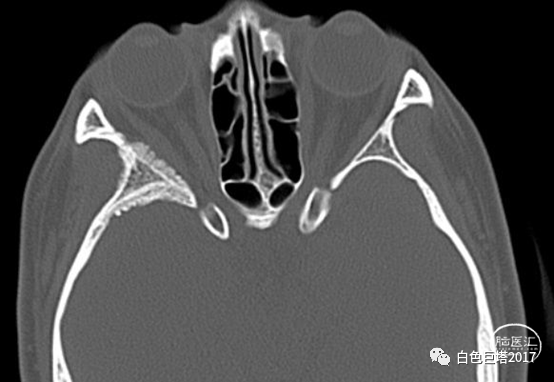

入院头颅CT检查提示右侧颞骨-眼眶后外侧壁骨质改变,眶内未见明显占位。报告考虑骨纤维异常增殖症可能性大。

3Dslicer重建可见眶后外侧壁骨质不均匀增厚,毛糙。

入院诊断:1.眼球突出原因待查(蝶骨嵴脑膜瘤?颅骨纤维异常增殖症?),2.视神经管狭窄,3.慢性鼻窦炎。

入院讨论病情,患者以突眼为主要症状,无眼球活动障碍,无炎性症状,无眶内占位,无甲状腺功能异常。结合患者入院头颅眼眶CT重建检查及既往MRI表现,考虑蝶骨嵴脑膜瘤可能,同时不能除外颅骨纤维异常增殖症。